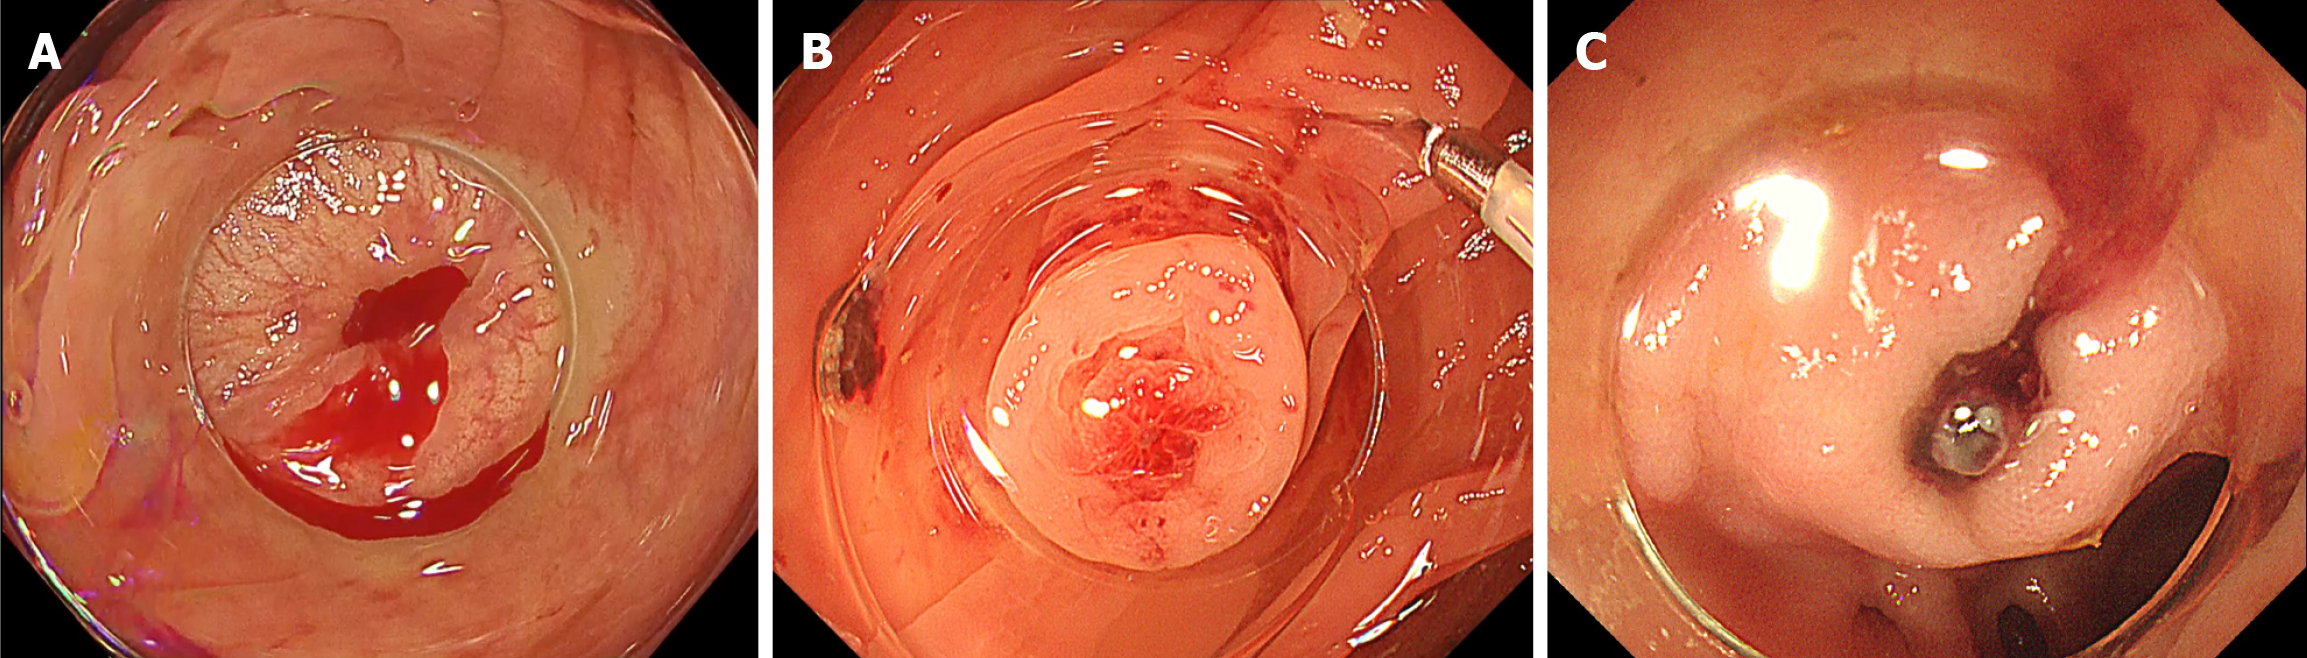

Consecutive patients hospitalized for acute hematochezia who underwent colonoscopy during the same admission were included. CDB was defined as either: (1) Definite CDB, in which clear SRH were identified within a diverticulum[15-17]; or (2) Presumptive CDB, in which no SRH was observed and no alternative bleeding source was identified[16-18]. SRH was defined as active bleeding (Figure 1A), non-bleeding visible vessels (Figure 1B), or adherent clots (Figure 1C) that developed into active bleeding or non-bleeding visible vessels upon removal[17,18]. Patients were excluded if the observation time could not be assessed or if trainees were involved in the colonoscopy, as limited technical proficiency could not only prolong insertion and observation times but also lead to an unjustified reduction in the SRH detection rate.